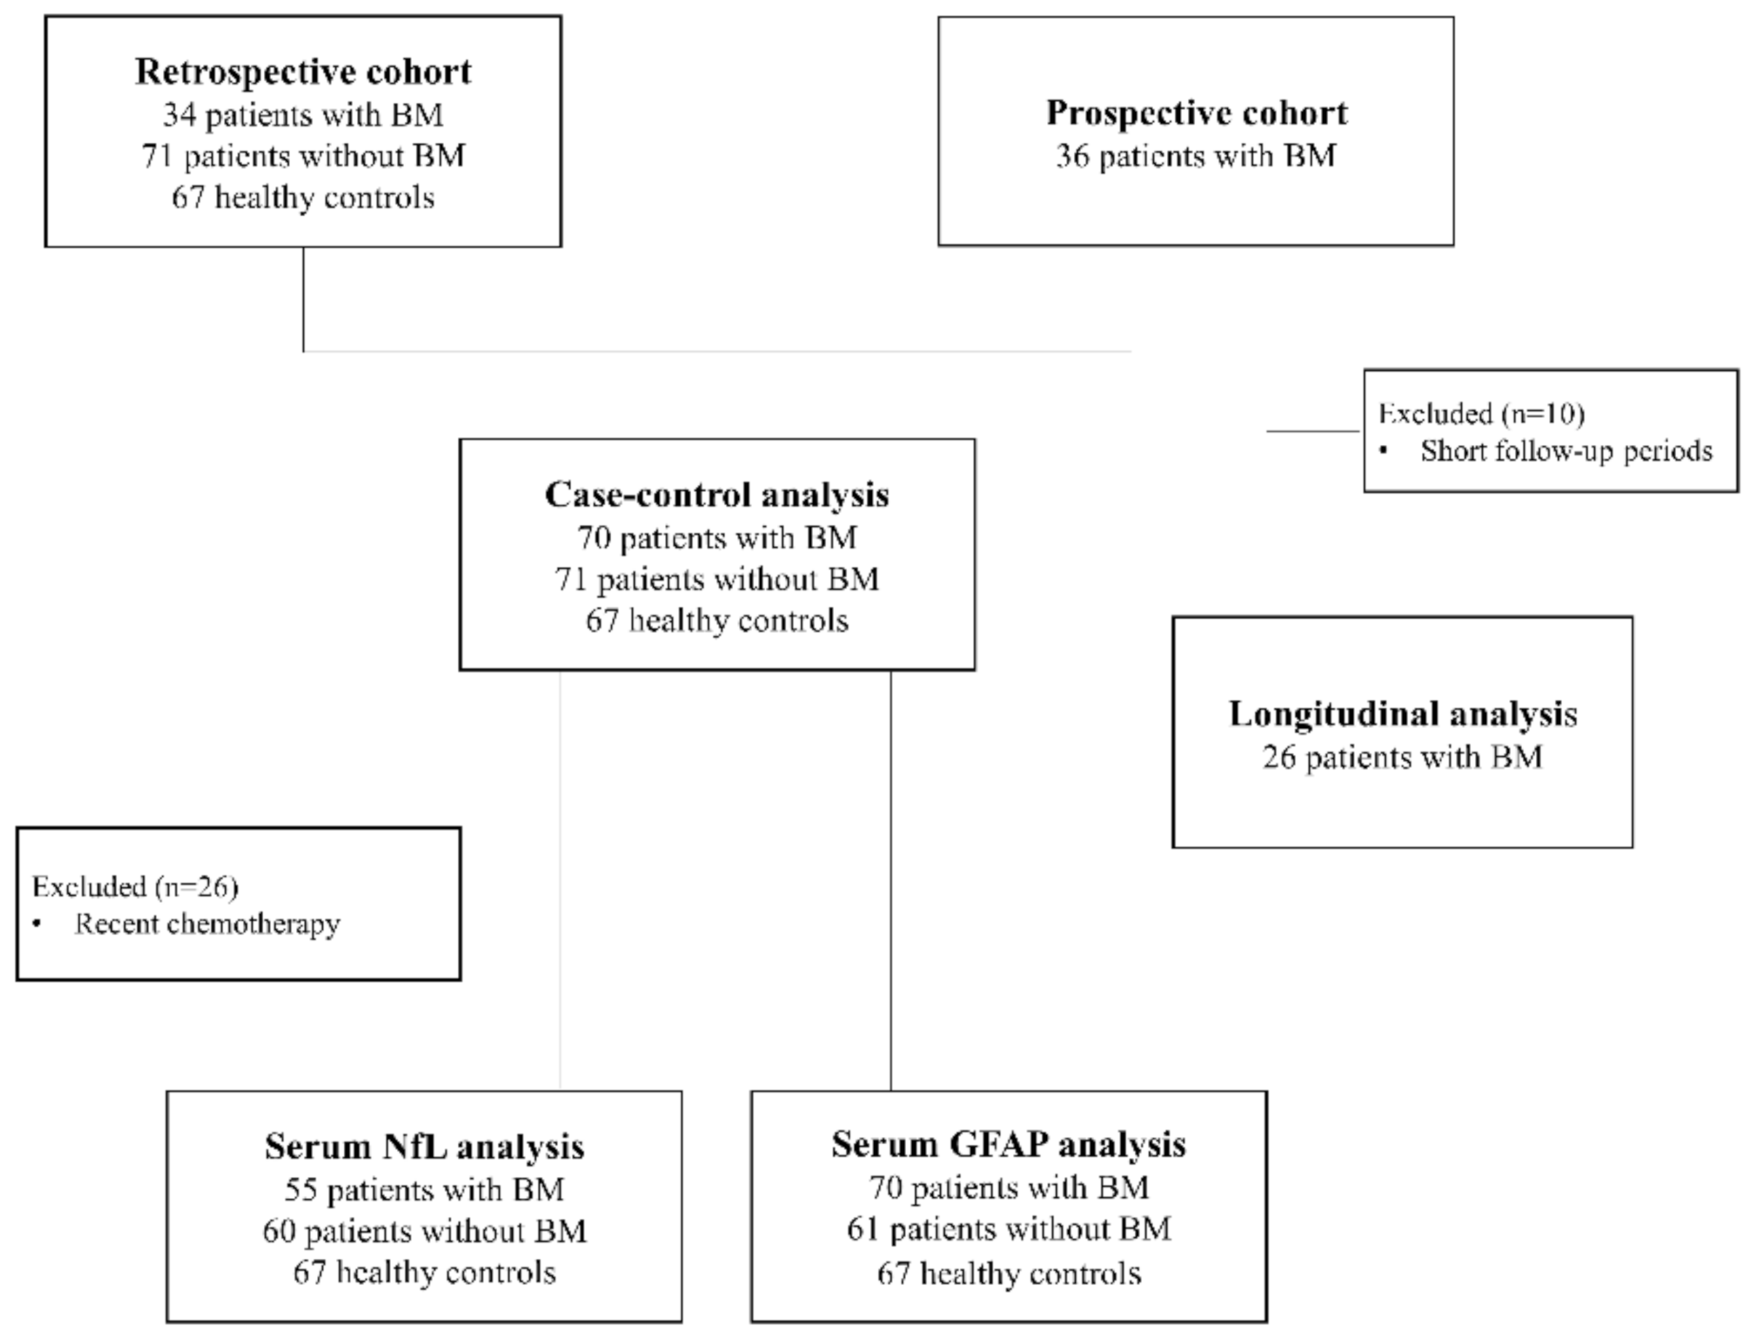

4. Materials and Methods

4.1. Study Design and Participants